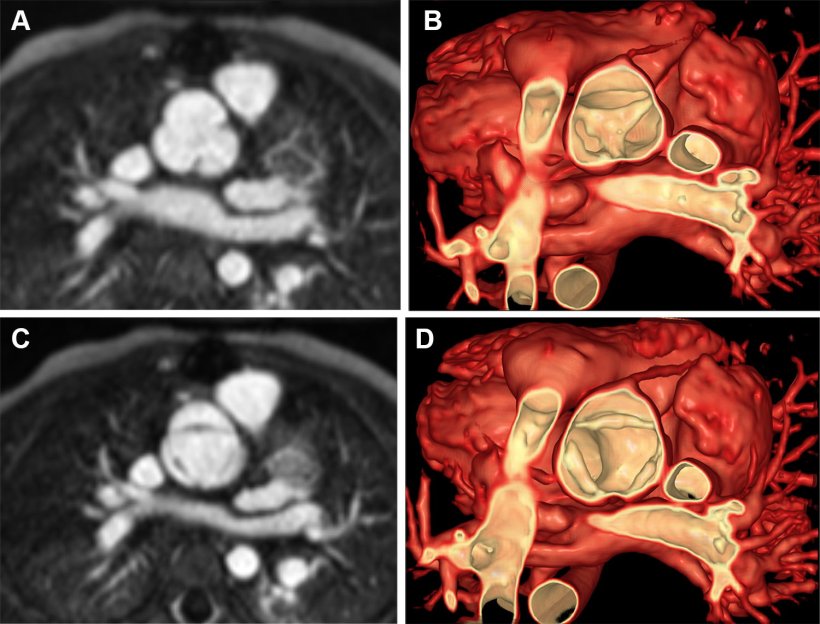

The team developed new ways to display blood flow on MRI, including lines showing the direction of flow and color-coded displays similar to those on Doppler ultrasound. While 3D ultrasound can also show tissue and flow together, it displays a smaller field of view, and the accuracy of flow measurements depends on the angle between the ultrasound beam and the blood flow direction, Dr. Jolley explained. CT can provide excellent anatomic images but cannot show blood flow, and it uses ionizing radiation. MRI provides high-quality flow images regardless of angles, and it does it without radiation—which is especially important for children who may need repeated imaging throughout their lives.

The team was excited to find that their MRI-based images looked quite similar to 3D echocardiography with color Doppler, which doctors are already familiar with and rely on for evaluating heart valves.